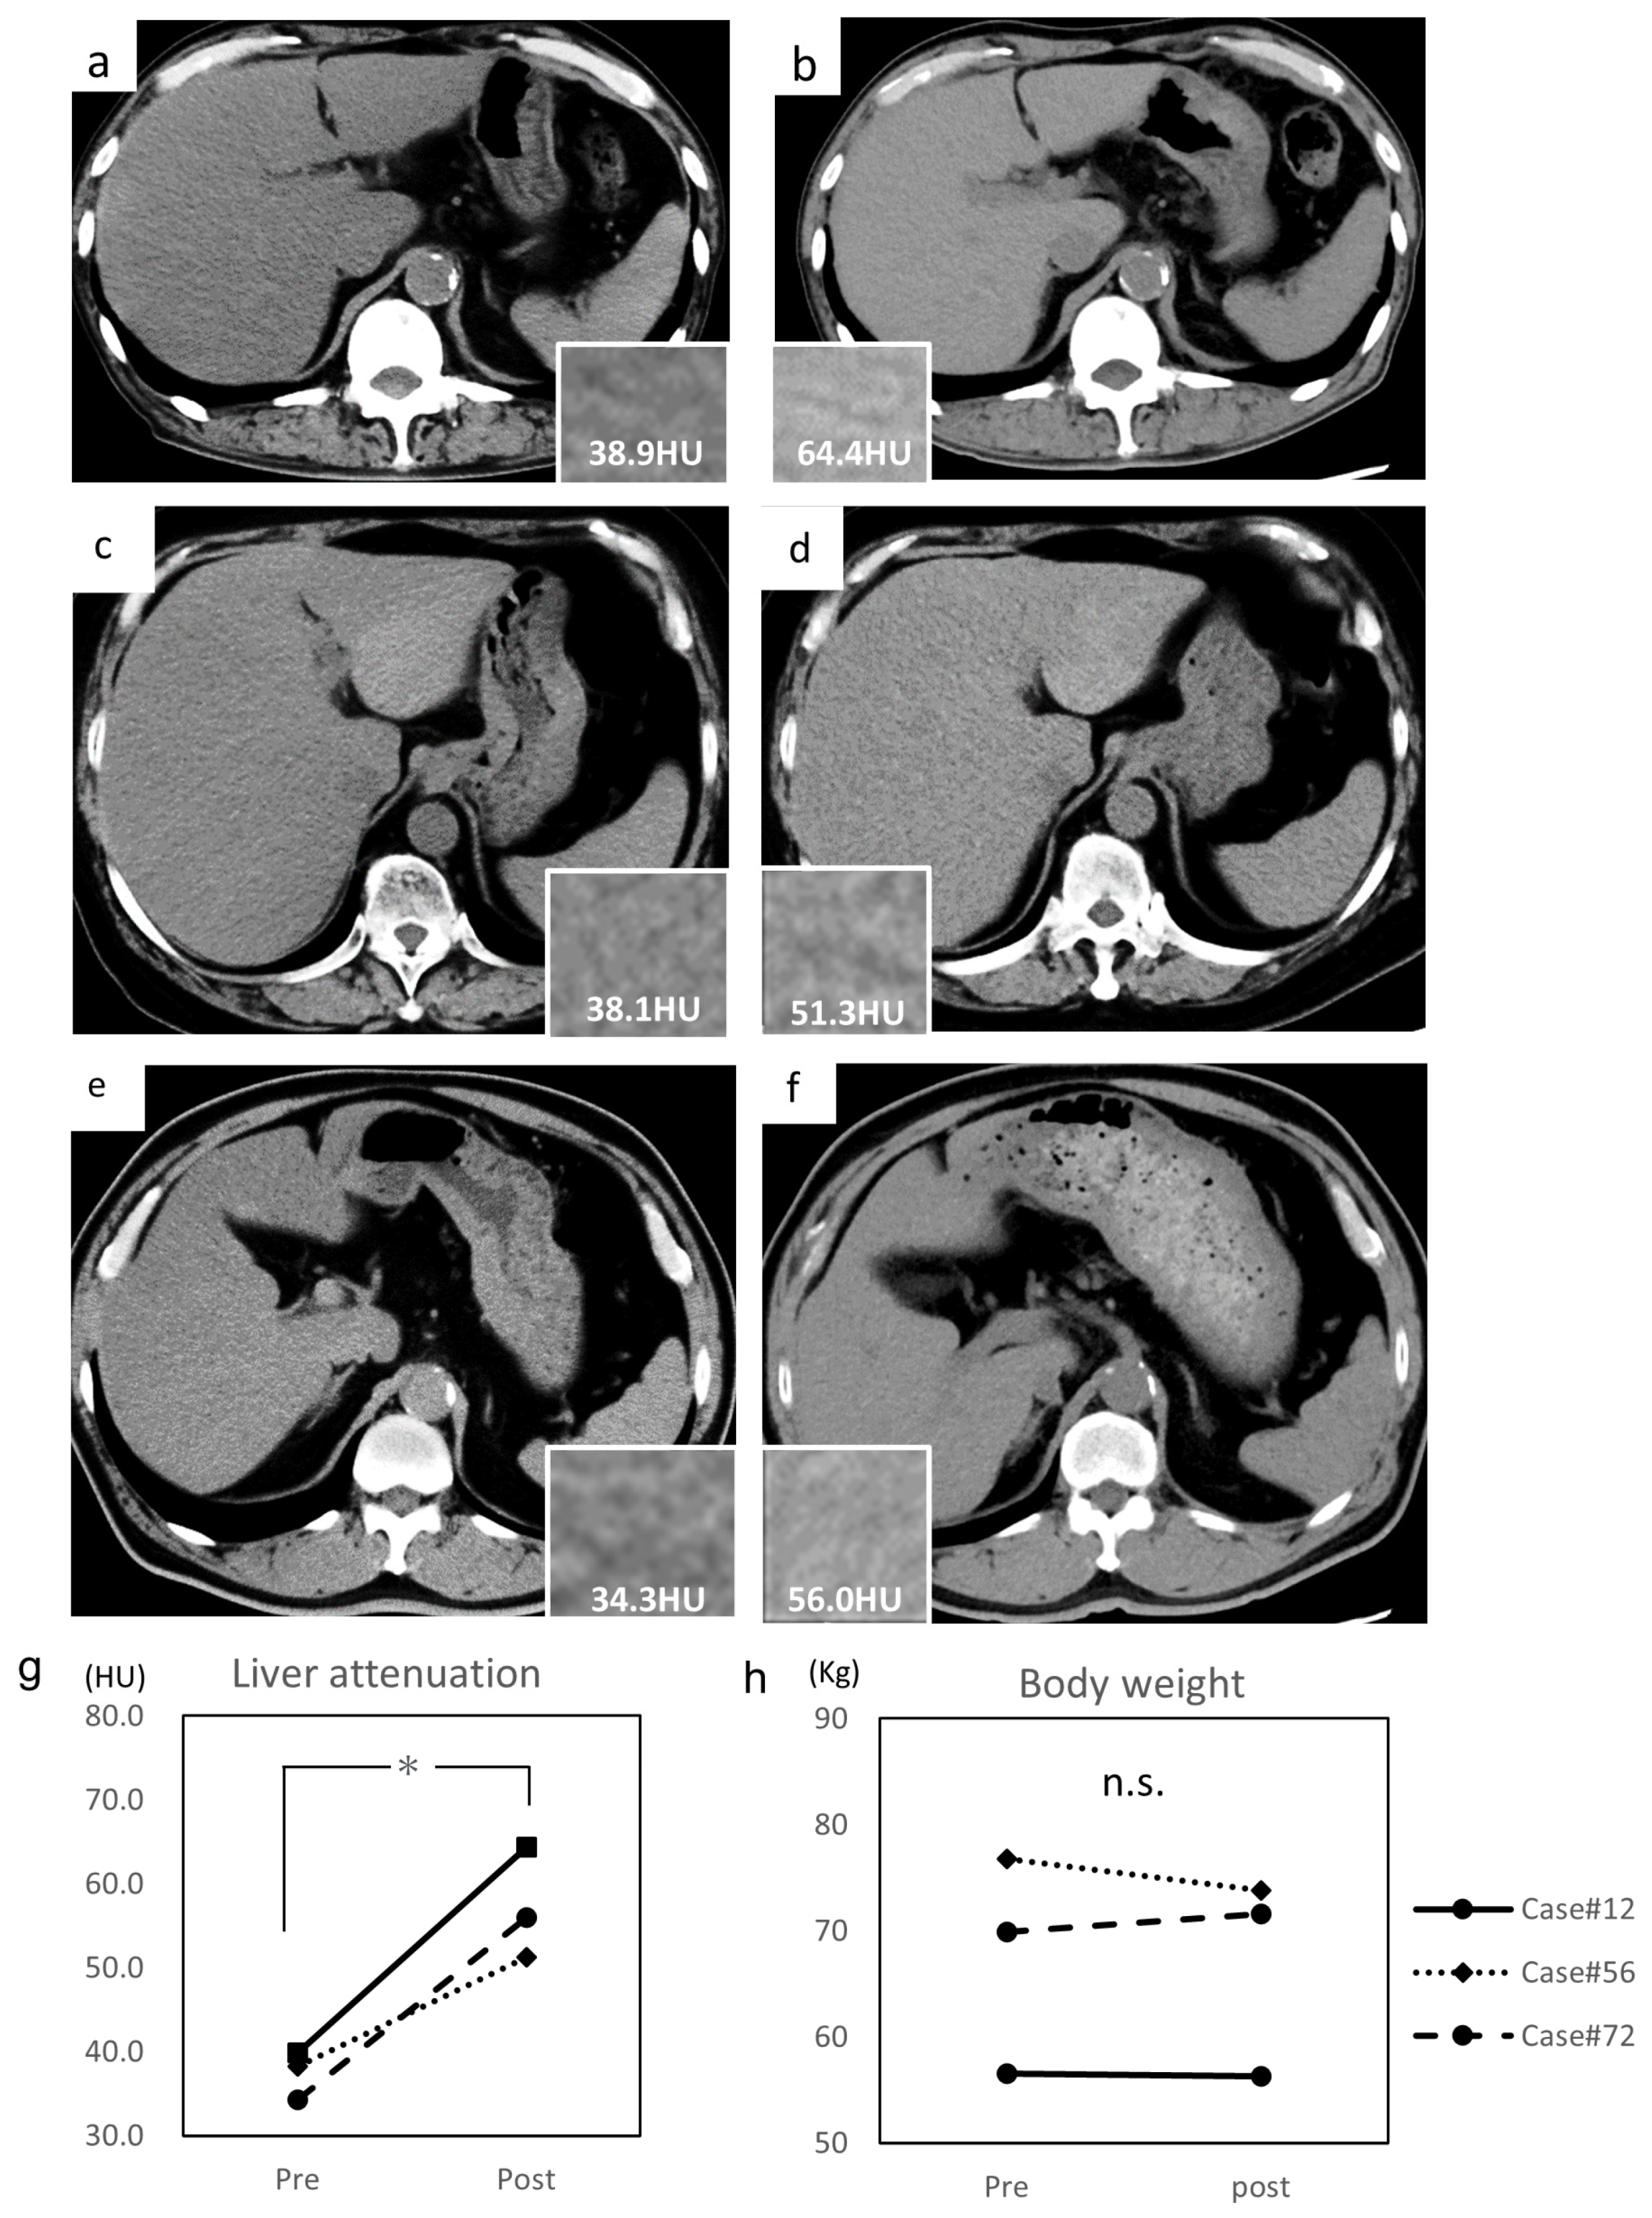

The median interval was 95.1 (range, 67–118) weeks. The average pre-treatment liver attenuations of Case #12, #56, and #72 were 38.9 HU (Figure 3a), 38.1 HU (Figure 3c), and 34.3 HU (Figure 3e), respectively. The average post-treatment liver attenuations of Case #12, #56, and #72 were 64.4 HU (Figure 3b), 51.3 HU (Figure 3d), and 56.0 HU (Figure 3f), respectively. The average liver attenuation significantly increased after treatment (39.1 ± 1.2 to 57.8 ± 2.7 HU, p = 0.028) (Figure 3g). The L/S ratio also significantly improved (0.76 ± 0.04 to 1.18 ± 0.02, p = 0.012). Their TG levels decreased and LFT performance increased (AST, 30.3 ± 4.0 to 20.3 ± 3.1 U/L; ALT, 39.3 ± 4.1 to 20.0 ± 8.2 U/L; GGT, 43.3 ± 4.3 to 27.7 ± 5.2 U/L); however, LDL-cholesterol (135.3 ± 22.4 to 137.7 ± 26.7 mg/dL), HbA1c (8.1 ± 0.7 to 7.7 ± 0.5%), and body weight (67.7 ± 4.9 to 67.2 ± 4.5 kg) (Figure 3h) did not significantly differ.

Figure 3.

Alteration of liver attenuation assessed by CT imaging. (a) Pre-treatment abdominal CT of Case #12, (b) post-treatment abdominal CT of Case #12, (c) pre-treatment abdominal CT of Case #56, (d) post-treatment abdominal CT of Case #56, (e) pre-treatment abdominal CT of Case #72, and (f) post-treatment abdominal CT of Case #72. (g) Alteration of liver attenuation assessed by CT imaging before and after treatment. Liver attenuations are indicated in each column. (h) Alteration of body weight before and after treatment. Hounsfield unit, HU. Data are expressed as mean with standard error of the mean (SEM). n.s. not significant, * p < 0.05.